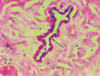

You perform an incisional biopsy on a unilocular radiolucent lesion of the left maxilla in the lateral incisor-canine area which is causing divergence of these tooth roots. A representative image of the biopsy specimen is shown below. What is the best diagnosis? A. Lateral periodontal cyst B. Odontogenic keratocyst C. Glandular odontogenic cyst D. Ameloblastoma E. Calcifying odontogenic cyst

B. Odontogenic keratocyst The image shows the architecture of a cyst, including a lumen, epithelial lining, and fibrous connective tissue wall, therefore choice D is incorrect. The exact type of cyst is determined by the features of the epithelial lining. The epithelial lining shown is ~6-8 cell layers thick, has a palisaded basal cell layer, and is covered by a corrugated surface of parakeratin. Therefore, the correct answer is B. A lateral periodontal cyst (A) will have a thinner lining (1-3 cells thick) with focal thickenings and no keratin. A glandular odontogenic cyst (C) will have a lining of variable thickness and other features including mucous cells, apocrine snouting, microcysts, and cilia. A calcifying odontogenic cyst (E) will have aberrant keratinocyte formation known as “ghost cells.”